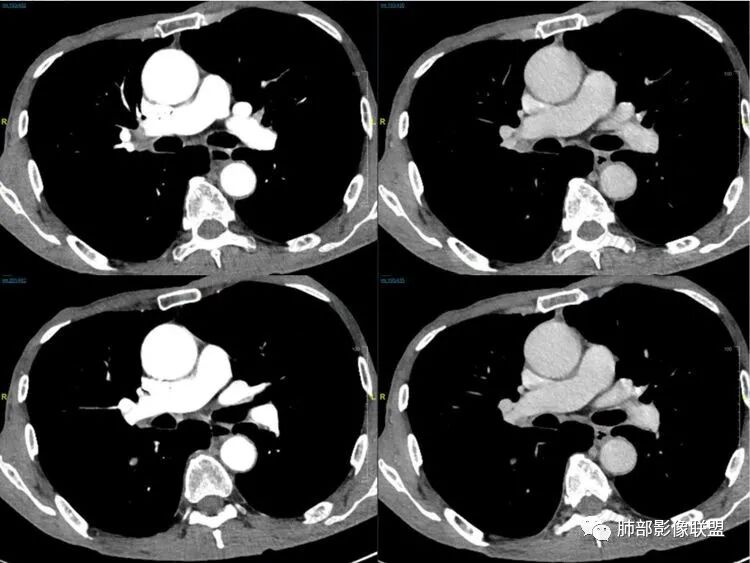

老年男性患者,胸部隐痛1月入院,有长期吸烟史,胸部CT:右肺下叶背段梭型结节灶,边界清晰,无明显分叶、毛刺及周边磨玻璃影,内部密度不均匀,支气管截断,增强扫描不均匀轻度强化,内部似乎见支气管黏液栓,纵隔淋巴结不大,考虑恶性病变:小细胞癌(缺少典型的纵隔肺门淋巴结增大融合),鳞癌(病史复合,但没有阻塞性肺炎,内部没有坏死,),类癌(多见于女性患者,与吸烟关系不大),首先考虑典型类癌,

老年男性,右肺下叶梭形或椭圆形结节,形态较规则,边缘光整,支气管截断,增强不均匀轻度强化,右肺门及纵隔淋巴结增大,考虑恶性病变,鳞癌或小细胞癌,神经内分泌癌(小细胞形)。

老年男性患者,右肺下叶背段梭形结节影,边界比较光整,密度均匀,没有明显的分叶毛刺,没有阻塞性肺炎的表现,这些感觉具备有良性的特点。而近端支气管截断,增强明显的强化,纵隔多发的淋巴结,显得是恶性的特点。总体印象,老年患者+支气管截断征象+明显强化的结节+纵隔多发淋巴结,还是考虑恶性结节,小细胞癌或是鳞癌。

男性,老年人,长期吸烟史,老慢支背景,右下肺背段占位,支气管亚段门口堵,病灶长轴与支气管平行,推测腔内生长可能,病灶内血管穿行,周围干净,轻度强化,右肺门淋巴结肿大,考虑恶性,神经内分泌癌(大小类)>淋巴上皮瘤样癌>腺癌>鳞癌

右肺下叶梭形实性结节,密度均匀,边缘光整,局部膨隆,近端支气管截断,轻度强化,血管走行自然,右肺门及纵隔淋巴结增大,考虑小细胞癌>鳞癌

右肺下叶背段结节,沿着支气管走行呈长椭圆形,边缘圆滑清晰,近端支气管阻塞,远端支气管有沿壁增厚,右肺门淋巴结肿大,中度强化,老年男性,吸烟病史,肺气肿背景,考虑小细胞肺癌,鉴别鳞癌

老年男性,吸烟史,右肺下叶梭形肿块,边缘平直有分叶,支气管近端阻塞,右肺门肿大淋巴结,增强后轻度强化,欠均匀,首先考虑恶性,小细胞肺癌?

老年男性+吸烟+右下肺肿块影+支气管截断+淋巴结肿大,考虑恶性,倾向小

老年男性,吸烟史,右肺下叶背段梭型软组织肿块,边缘膨隆,不均匀强化,近端支气管截断,同侧肺门及纵隔淋巴结肿大,支持恶性,小细胞可能大,鳞癌缺少阻塞性改变

晨读,右下叶梭形占位,边界光滑,支气管截断,可见尾征,不均匀轻度强化,肺门淋巴结肿大,有吸烟史,高龄高危患者,首先考虑恶性,考虑小细胞癌,鉴别一下鳞癌

老年男性,前胸隐痛1月。2年前有白内障手术史。右下肺结节,沿中轴呈梭形,膨隆,边清、无分叶,无毛刺,近端支气管截断完全堵塞,病灶以远未见阻塞性炎症及肺不张。内部密度基本均匀,增强轻微强化,似见局部低密度影。纵隔及右肺门见肿大淋巴结。整体考虑恶性可能性大,小细胞癌?鳞癌?注意鉴别良性结节—错构瘤。

老年男性,长期吸烟史,右肺下叶背段梭形低密度灶,边界清晰,无明显分叶、毛刺,边缘稍彭隆,支气管截断,右肺门淋巴结增大,增强扫描不均匀轻度强化(延迟略明显),首先考虑恶性,小?不典型结核球待排。

右肺下叶背段结节,气管堵塞,密度均匀,边界清晰,无明显分叶、毛刺,边缘膨隆,右肺门淋巴结增大,增强轻度强化,考虑小细胞癌,鉴别鳞癌。

右肺下叶梭形软组织结节,密度均匀,明显尾巴,边缘光整,近端支气管截断,轻度强化,血管走行自然,又腊肠尾巴征象

考虑恶性  小细胞癌?

男,83,前胸部隐痛不适1月。有长年大量吸烟史。胸部CT:肺气肿,右肺下叶纺锤型实性结节灶,边界清晰,支气管截断,内部密度不均匀,增强扫描不均匀强化,右肺门淋巴结大。考虑恶性病变:小?鳞?鉴别炎性肉芽肿、错构瘤等。

晨读:老年男性+吸烟+右肺下叶与气管长轴一致的梭形肿块影+支气管截断,轻度强化,右肺门肿大淋巴结,考虑恶性,小细胞肺癌可能,鉴别鳞癌

呈典型管状改变,近端支气管堵塞、稍扩张,病灶有强化倾向于恶性,没有强化倾向于炎性病变(结核之类);近端呈结节状(鳞癌多一些),这个病例呈管状(小细胞Ca多一些);平扫与强化有差异,有轻度强化,是粘液栓还是血管?